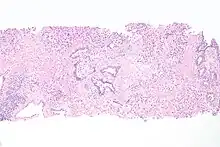

| Histopathology of transitional carcinoma of the urinary bladder. Transurethral biopsy. Hematoxylin and eosin stain. | |

Histopathology of urothelial carcinoma of the urinary bladder, showing a nested pattern of invasion. Transurethral biopsy. H&E stain

Histopathology of urothelial carcinoma of the urinary bladder.